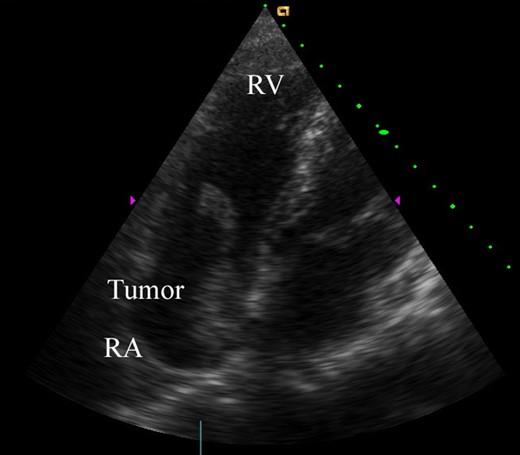

A 74-year-old male patient was referred to our hospital for the treatment of a right atrial tumor. He had experienced the sudden onset of dyspnea and had gone to another hospital. There, transthoracic echocardiography revealed the right atrial tumor. After his transfer to our hospital, transthoracic echocardiography was performed again. The right atrial tumor, which adhered to the interatrial septum, had a tail-like surface projection. The tumor projection was mobile and prolapsed into the right ventricle during diastole (Fig. 1). In addition, the right cardiac cavities were dilated and the estimated right ventricle pressure was 63 mmHg, which suggested the presence of moderate pulmonary hypertension. Subsequently, computed tomography (CT) showed that the left pulmonary artery was occluded by a large embolus (Fig. 2). Because the embolus formed acute angles with the vessel wall, acute pulmonary embolism was highly suspected. We performed an emergency surgery for the removal of both the right atrial tumor and the embolus in the left pulmonary artery.

Preoperative transthoracic echocardiography. The right atrial tumor (40 × 20 mm) originated from the interatrial septum. The tumor had a tail-like surface projection, which prolapsed into the right ventricle during diastole. RV, right ventricle; RA, right atrium.